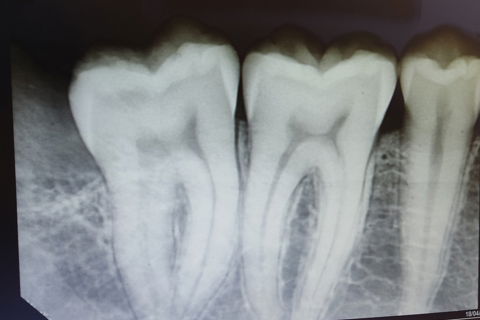

28 antes

rx 28 pos